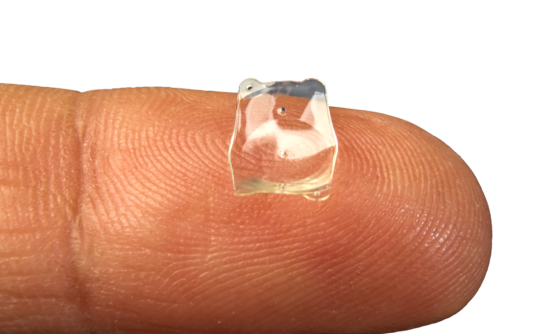

Die implantierbare „Kontaktlinse“

Die EVO ICL ist eine klare Linse aus Kunststoff, die einer Kontaktlinse ähnelt. Da sie klein und extrem weich ist, kann sie problemlos gefaltet werden und mit einem Injektor innerhalb von Sekunden – durch einen kleinen Zugang in der Hornhaut – sanft im Auge platziert werden.

Die implantierbare „Kontaktlinse“

Die EVO ICL ist eine klare Linse aus Kunststoff, die einer Kontaktlinse ähnelt. Da sie klein und extrem weich ist, kann sie problemlos gefaltet werden und mit einem Injektor innerhalb von Sekunden – durch einen kleinen Zugang in der Hornhaut – sanft im Auge platziert werden.